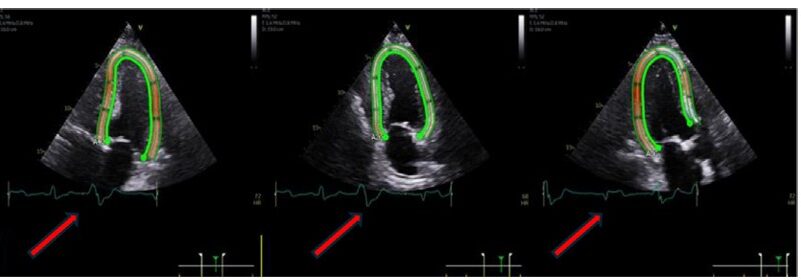

(6) Atenção aos tempos da diástole final e sístole final durante o ciclo cardíaco – ficar de olho no traçado eletrocardiográfico e suas marcações.